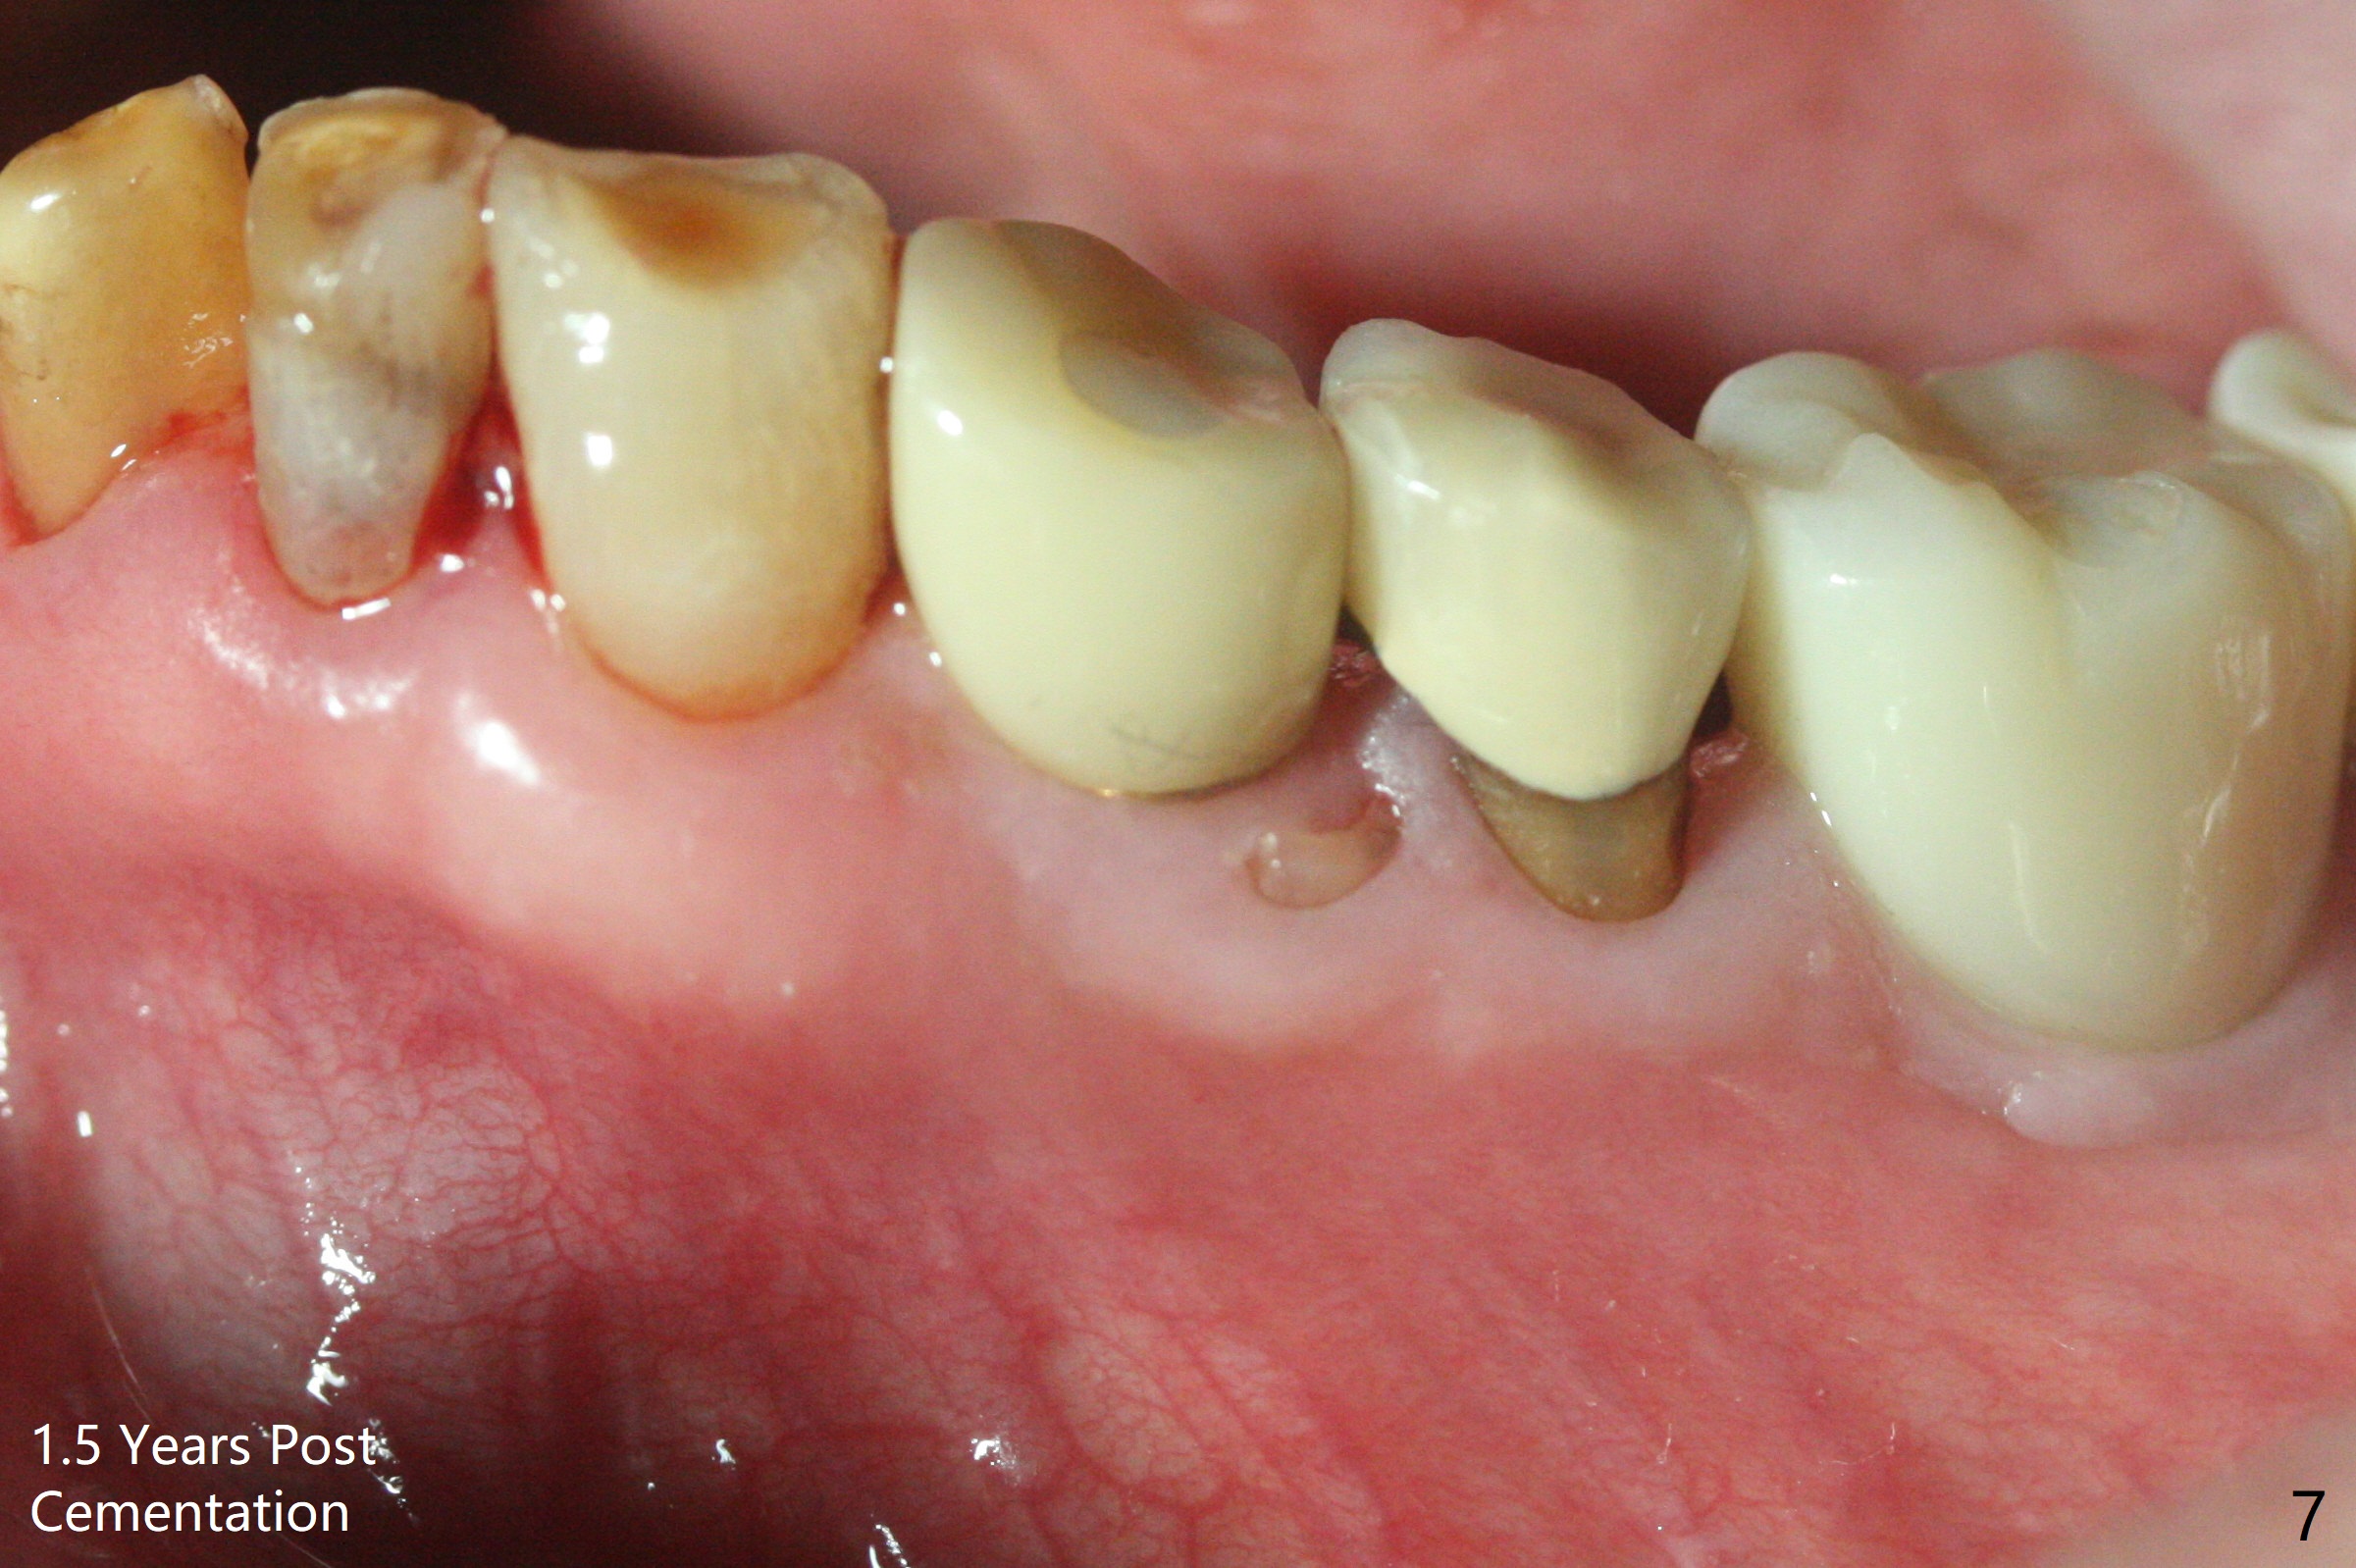

Extraction of the fractured tooth at #21 is as difficult as #19 (requiring incision). Because of the long root and hemorrhage, the apex of the tooth (Fig.1 black *) and a thin layer of the buccal shield (white *) remain when osteotomy is initiated. Due to hard bone, a 3.8x11.5 mm implant achieves insertion torque of ~35 Ncm (Fig.2); with placement of a 4.5x4(3) mm abutment, an immediate provisional is fabricated. There is limited remaining space for bone graft. The patient will return for final restoration 4 months postop; the buccal plate will be expected to have not collapsed! The implant seems to be osteointegrated, while the root piece (socket shield *) is exposed 4 months postop (Fig.3). The socket shield seems to be harmless, difficult to trim without local anesthesia and associated with no buccal plate concavity (Fig.4,5 <). With socket shield at #21, the crown looks normal, whereas the one at #19 without socket shield looks long, suggesting vertical bone loss early postop (before restoration, Fig.6).没有牙根处,角化龈少(图七,与术前(图八)对比)。